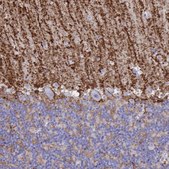

Application

The Human Protein Atlas project can be subdivided into three efforts: Human Tissue Atlas, Cancer Atlas, and Human Cell Atlas. The antibodies that have been generated in support of the Tissue and Cancer Atlas projects have been tested by immunohistochemistry against hundreds of normal and disease tissues and through the recent efforts of the Human Cell Atlas project, many have been characterized by immunofluorescence to map the human proteome not only at the tissue level but now at the subcellular level. These images and the collection of this vast data set can be viewed on the Human Protein Atlas (HPA) site by clicking on the Image Gallery link. We also provide Prestige Antibodies® protocols and other useful information.

- IHC tissue array of 44 normal human tissues and 20 of the most common cancer type tissues.